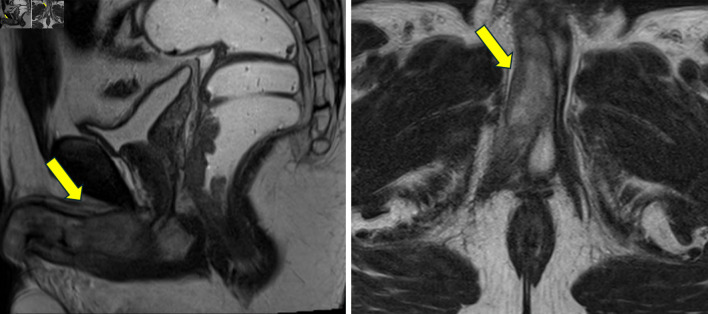

结直肠癌(CRC)向海绵体转移是一种非常罕见的疾病,通常与全身传播和预后不良有关。它常与肝脏和淋巴结累及同时出现。男性,43岁,会阴疼痛,直肠出血,尿路梗阻症状。影像学检查显示kras突变的直肠腺癌,分类为IV期,同步转移到海绵体和肝脏。治疗开始时采用FOLFOXIRI(亚叶酸、5-氟尿嘧啶、奥沙利铂和伊立替康)化疗,但由于肿瘤溶解综合征和与UGT1A1突变相关的毒性而停止。尽管改良FOLFOX(亚叶酸、氟尿嘧啶、奥沙利铂)加贝伐单抗,但病情进展迅速,促使患者转向姑息治疗,随后死亡。海绵体累及CRC反映疾病进展,经常伴有同步转移和有限的预期寿命。该病例强调了此类转移的不良预后意义,提示盆腔淋巴扩散可能是一种机制,并强调了药物遗传学对治疗耐受性和结果的关键影响。文献回顾强调了这种表现的侵略性生物学。结直肠癌的阴茎转移是罕见的,但具有破坏性,表明疾病是播散性的。多学科管理应优先考虑症状控制,并保留针对特定病例的靶向治疗。本病例说明有泌尿系统症状的恶性肿瘤病史的患者需要加强临床怀疑。

Metastasis to the cavernous bodies from colorectal cancer (CRC) is an exceptionally rare condition, typically associated with systemic dissemination and an ominous prognosis. It often presents synchronously with liver and lymph node involvement. A 43-year-old male presented with perineal pain, rectal bleeding, and urinary obstructive symptoms. Imaging studies revealed a KRAS-mutated rectal adenocarcinoma, classified as stage IV, with synchronous metastases to the cavernous bodies and liver. Treatment was initiated with FOLFOXIRI (folinic acid, 5-fluorouracil, oxaliplatin and irinotecan) chemotherapy but was discontinued due to tumor lysis syndrome and toxicity linked to a UGT1A1 mutation. Despite modified FOLFOX (folinic acid, fluorouracil, oxaliplatin) plus bevacizumab, the disease progressed rapidly, prompting transition to palliative care and subsequent death. Cavernous body involvement in CRC reflects advanced disease, frequently accompanied by synchronous metastases and a limited life expectancy. This case underscores the poor prognostic significance of such metastases, suggests pelvic lymphatic spread as a likely mechanism, and highlights the critical impact of pharmacogenetics on treatment tolerance and outcomes. A review of the literature emphasizes the aggressive biology of such presentations. Penile metastases from CRC are rare but devastating, indicating disseminated disease. Multidisciplinary management should prioritize symptom control, with targeted therapies reserved for select cases. This case illustrates the need for heightened clinical suspicion in patients with a history of malignancy presenting with urological symptoms.